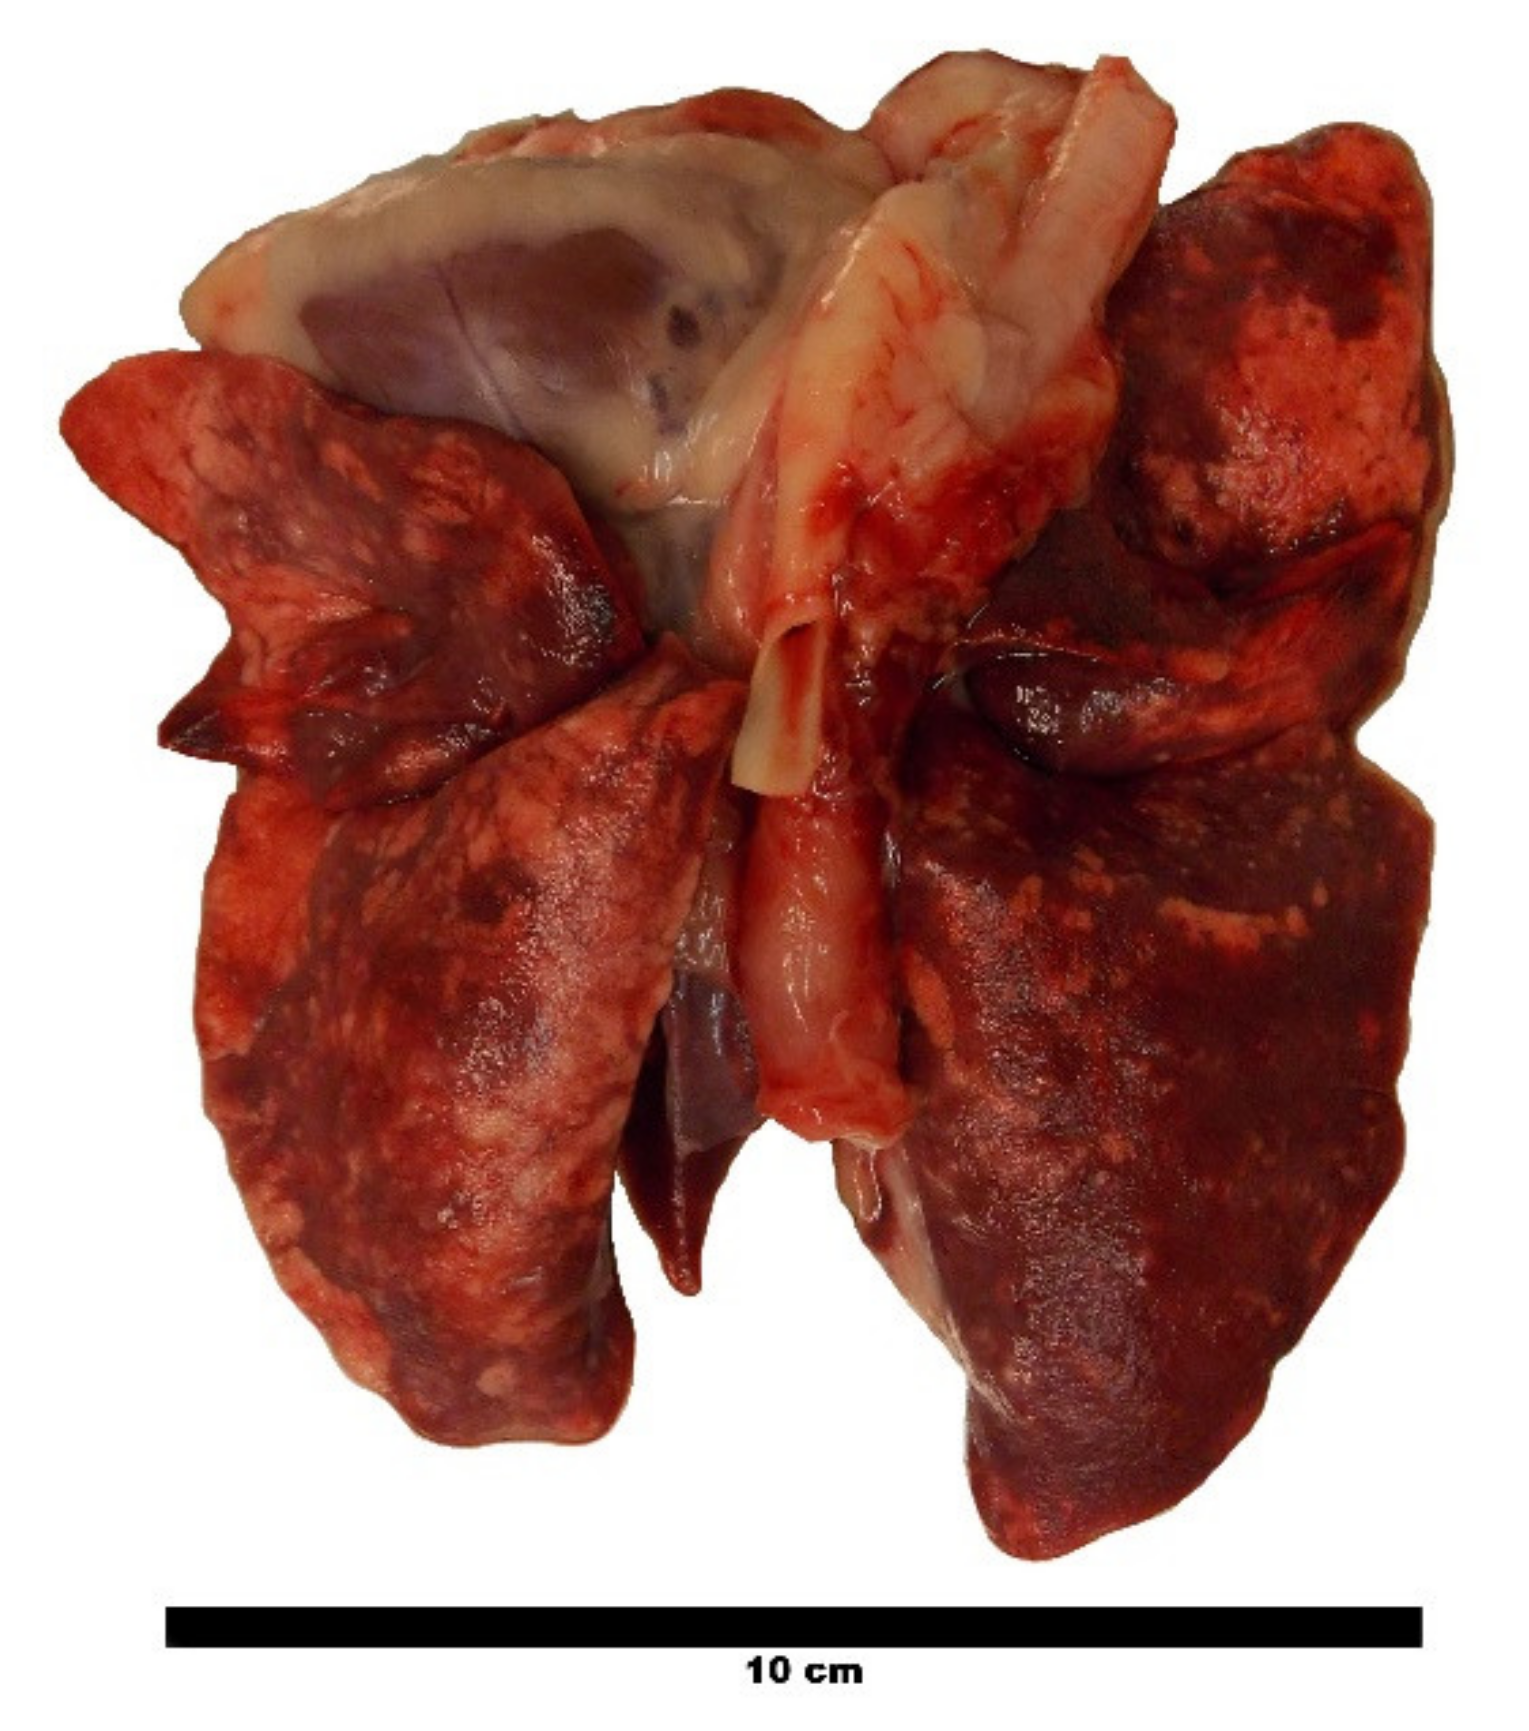

2.6. Post Mortem Nematode Counts